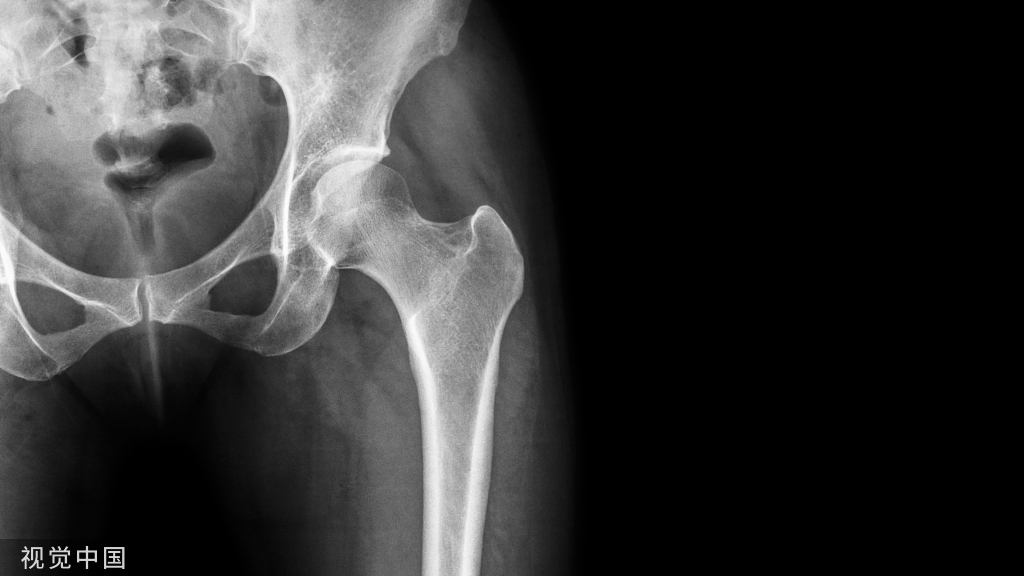

摔倒或车祸后髋部疼痛的患者急诊经常可见,临床医生会常规给他们行影像学检查如骨盆前后位、髋关节正侧位 X 线片等,明确是否存在骨折。

对于这类患者的 X 线片,需仔细观察:① 双侧股骨头及关节间隙的对称性② 髋臼及泪滴的完整性③ 4 个重要骨性标志的连续性:代表前柱的髂耻线、代表后柱的髂坐线、髋臼前缘和髋臼后缘

尽管仔细检查和评估,仍有一些外伤后髋部疼痛的患者,存在 X 片上难以发现的隐匿性髋部骨折。这种情况下,可以选择对骨髓水肿高度敏感的 MRI 进行随访(图 1)。

图 1 长跑运动员股骨隐匿性、应力性骨折。A 为髋部正位 片,虽未见明显骨折,但股骨颈基底部可见一模糊的线性硬化带(箭头)B 为 MRI 冠状位 STIR 序列扫描,示股骨颈应力侧可见一线性低密度信号影,周围包绕骨髓水肿的高密度影

从这个案例来看,长期运动的患者,如果出现髋部疼痛,X 线即使无特殊表现,也应考虑应力性骨折的可能性。